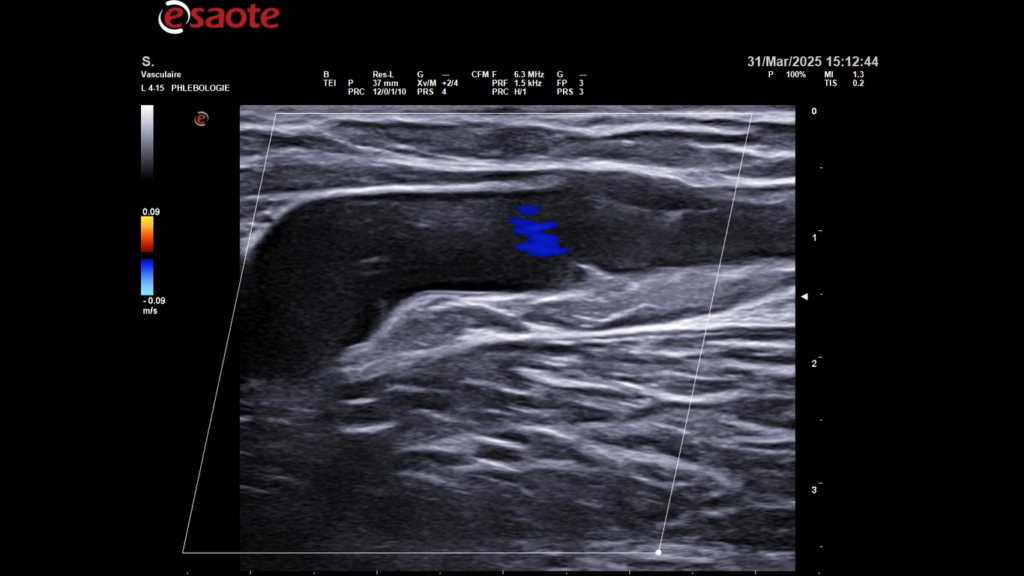

Formation pratique à la sclérothérapie échoguidée à la mousse – Expert 3D – 28 novembre 2025

L’EIS vous propose une formation d’une journée, le vendredi 28 novembre 2025, directeur du cours : Dr Mario Sica, cette session vous permettra d’optimiser la prise en charge diagnostique et thérapeutique de vos patients grâce à une approche avancée de la sclérothérapie échoguidée en 3D.